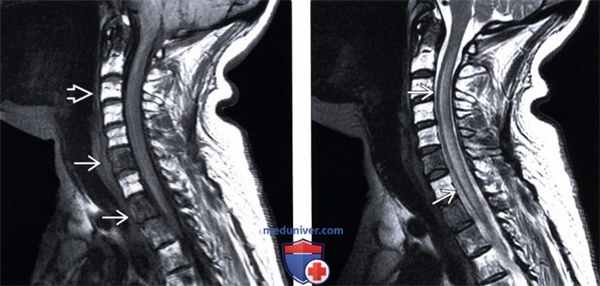

(Слева) Сагиттальный срез, Т1-ВИ: множественные метастатические очаги в телах шейных и верхнегрудных позвонков с признаками перестройки костного мозга после проведенной лучевой терапии. Спинной мозг несколько утолщен.

(Справа) Сагиттальный срез, Т2-ВИ: продольно распространенное усиление сигнала паренхимы спинного мозга и некоторое его утолщение. Подобная картина отека не является специфической, поэтому всегда необходимо исключить метастатическое поражение спинного мозга и пострадиационные изменения.

(Слева) Сагиттальный срез, Т1-ВИ с КУ: типичная картина па-ранеопластической миелопатии с фокальным симметричным контрастным усилением сигнала центральных столбов спинного мозга. Подобной симметричной картины при метастатическом поражении или пострадиационных изменениях не будет.

(Справа) Сагиттальный срез, Т1-ВИ с КУ, пациент с фокальным метастатическим поражением спинного мозга: строго ограниченное контрастирование очага опухоли в сочетании с продольно распространенными паранеопластическими изменениями спинного мозга.